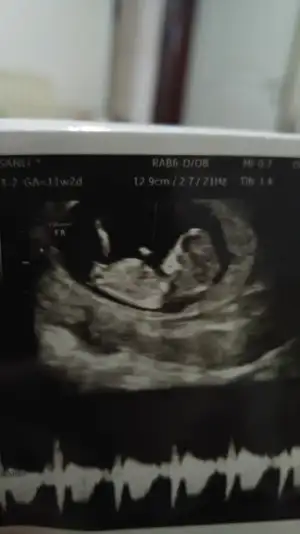

Teşekkürler uc tane usg var şuan elimde bgnun paylaşıyorum hemen, heyecanla yorumunuzu bekliyorum 😊😊😊💕

• 20200127_195653_HDR.webp

20200127_195653_HDR.webp

11,6 KB · Görüntüleme: 39

• 20200127_195645_HDR.webp

20200127_195645_HDR.webp

13,7 KB · Görüntüleme: 34

• 20200127_195456_HDR.webp

20200127_195456_HDR.webp

12,4 KB · Görüntüleme: 33

Evet ilk hayırlısıyla 12 de tekrar paylasicam bakalim degisiklik olucak mi 😊 hislerim erkek yonunde isteğimse kız kısmet artık